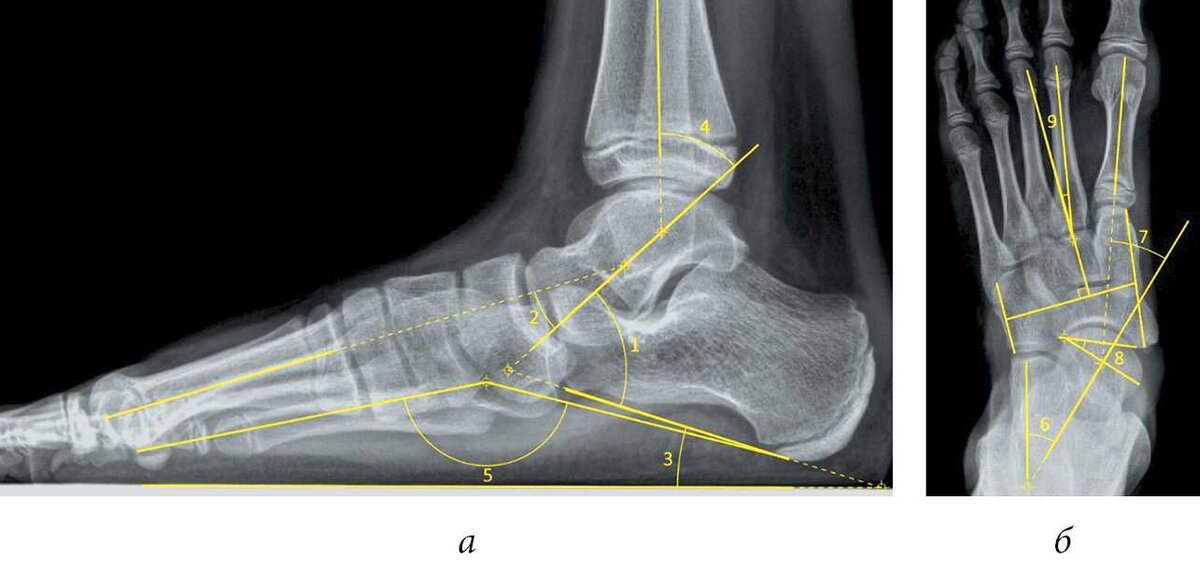

Давайте разбираться для чего нужны эти самые стельки и нужны ли они условно здоровому человеку. Итак наша стопа это сложнейший механизм. Состоит из огромного количества мышц, костей и суставов. Не просто так наша стопа имеет такое строение, все это работает как четкий часовой механизм. представьте себе купол, для того чтобы снизить ударность этот купол расплющивается, тем самым не передавая нагрузку на вышележащие суставы и кости и главное не давая сотрясению дойти до мозга. А теперь представьте, что вы под этот купол ортопедическую стельку подкладываете, которая не дает ему расплющиться. Соответственно не дает стопе произвести свою работу. Теперь представьте, что стопа постоянно находится в стельках, постоянно мышца, которая должна растянуться этого не делает, функцию свою теряет. Мышцы укорачиваются, спазмируются, перестают двигаться маленькие суставы в стопе, затем деградируют, деформируются и часто болят.